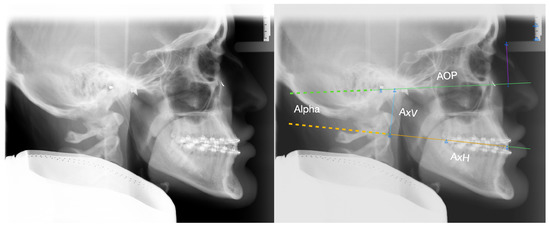

| 323 | 7.6 | 5.3 | 191 | 6.5 | 5.0 | ||

| AxV | 323 | 30.2 | 5.7 | 191 | 35.8 | 5.7 | <0.001 |

| AxH | 323 | 88.0 | 6.7 | 191 | 93.1 | 8.1 | <0.001 |

| 128 | 7.8 | 3.4 | 204 | 11.1 | 3.3 | 182 | 2.4 | 4.0 | <0.001 | ||

| AxV | 128 | 36.2 | 4.6 | 204 | 26.5 | 3.8 | 182 | 35.9 | 4.5 | <0.001 1 | |

| AxH | 128 | 98.9 | 5.5 | 204 | 88.1 | 5.4 | 182 | 85.6 | 5.6 | <0.001 | |